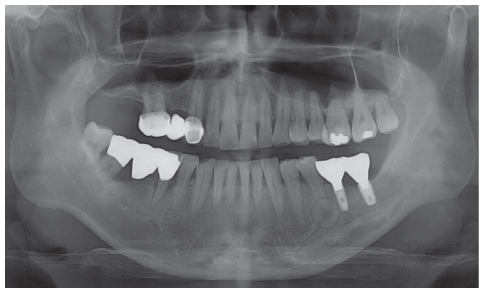

Figure 3

Periapical view taken 2 years ago.

Figure 3 Periapical view taken 2 years ago.